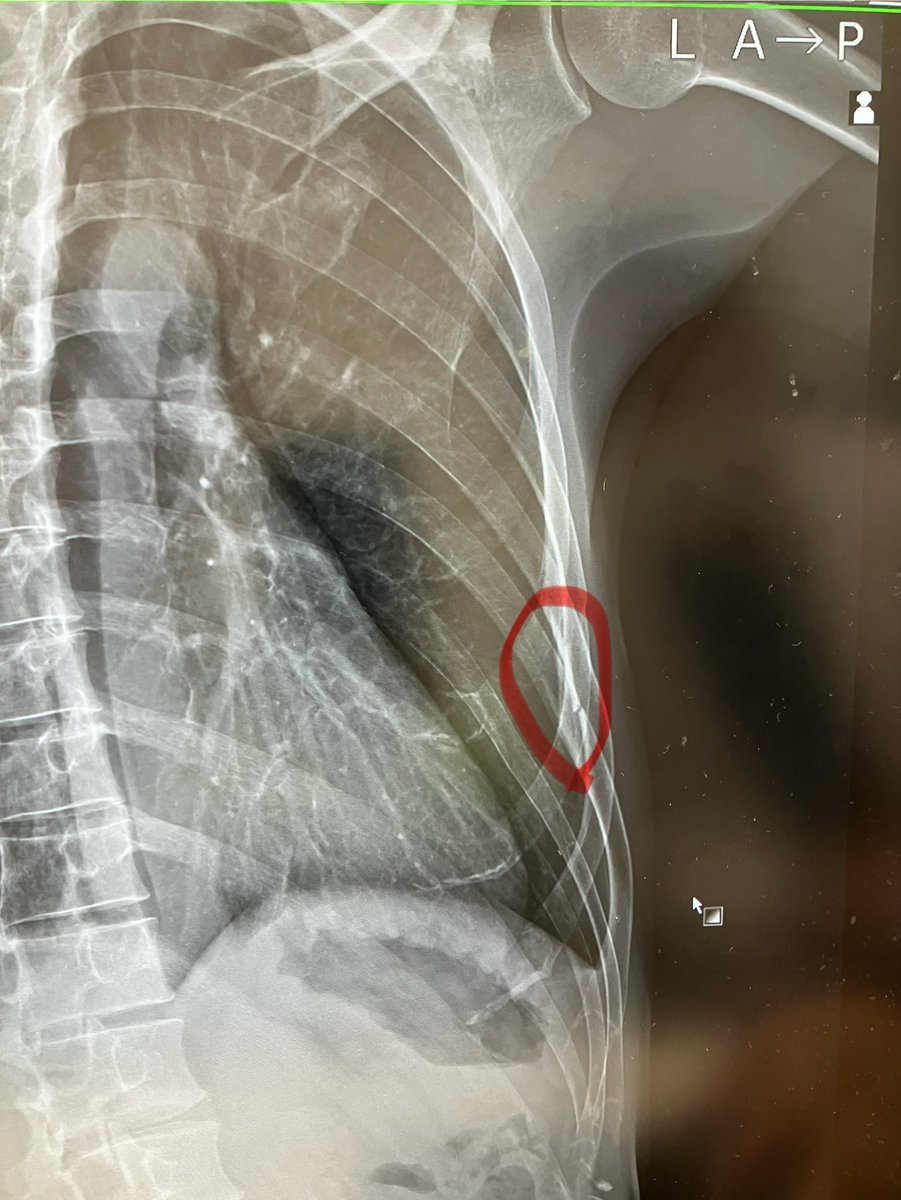

【悲報】転倒により骨折 転んだ先にあった鉄骨のフレームに胸を激しく打ちつけてしまい、肋骨が3本も折れました😇 明日の東海大記録会DNSは仕方ないとして、来月のつくば間に合うのかしら…?